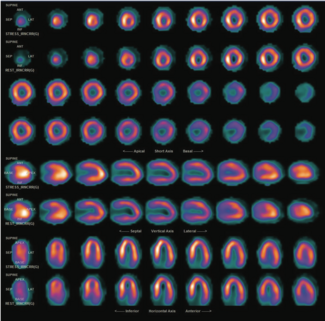

A 57-year-old male with a history of hypertension, end-stage renal disease on hemodialysis, and diabetes mellitus type 2 was found to have an anomalous left coronary artery on coronary angiography that was initially performed for the...